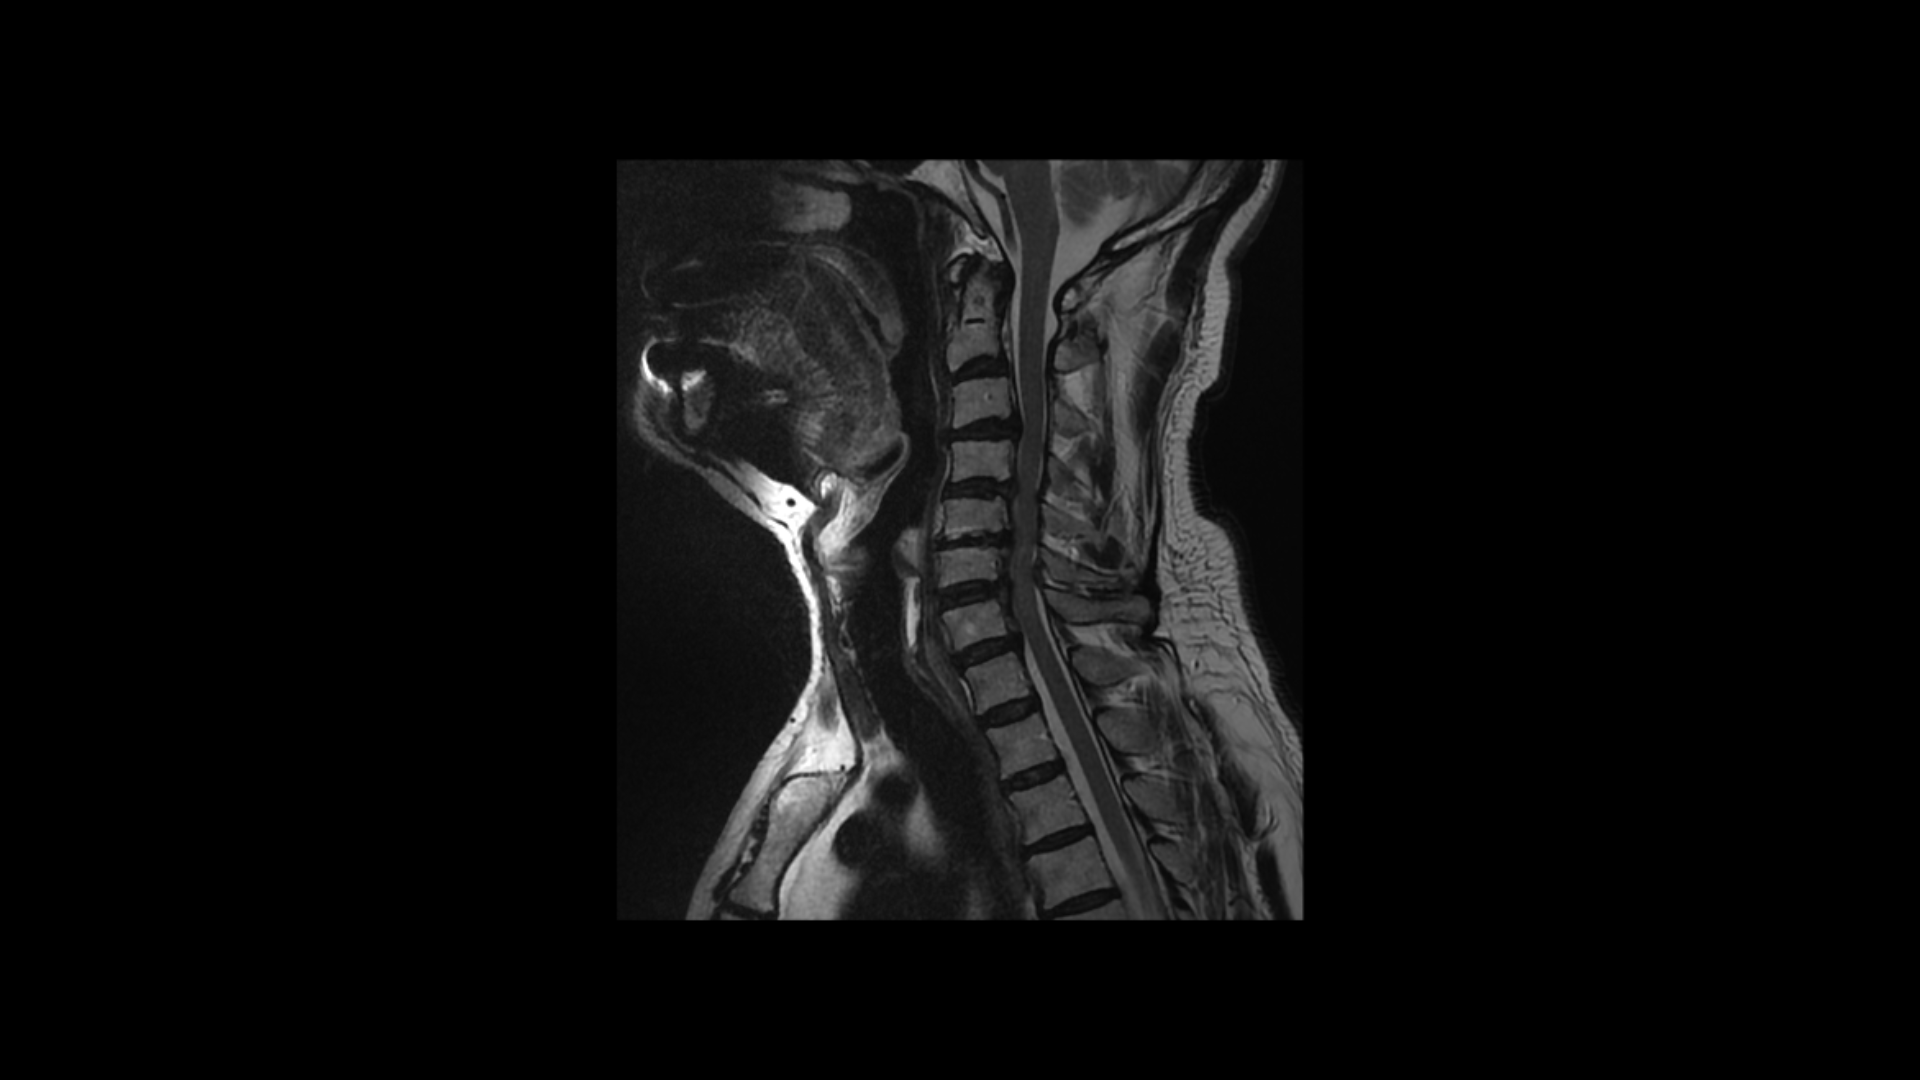

이분 MRI에서 보시다시피 전체적으로 목의 한마디만 제외하고 여러 마디가 다 안 좋습니다.